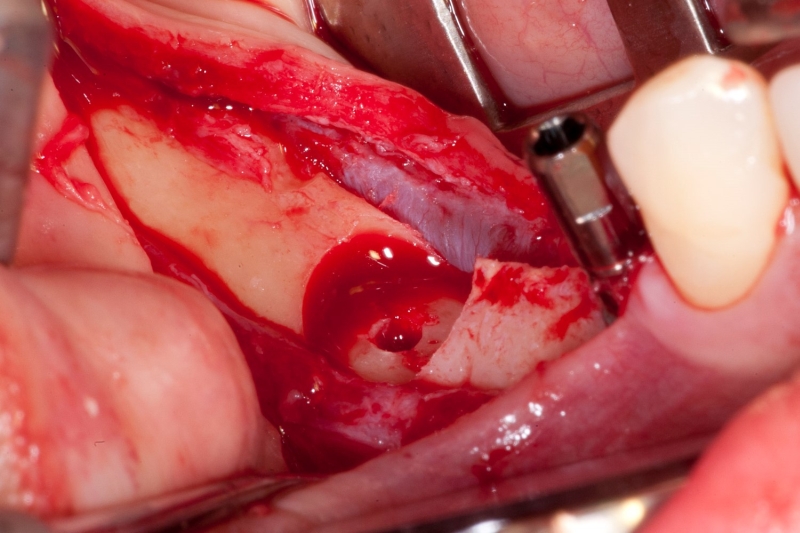

10/18 - Placement of maxgraft® bonering

11/18 - Implant insertion passing through maxgraft® bonering from the crestal side